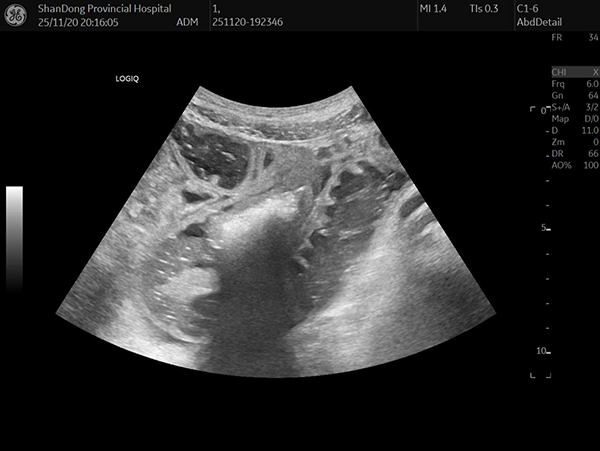

超声诊疗科主任医师刘翠红带领进修医师张修丽、相林以及规培医师、研究生等,通过胃肠超声实时动态监测,实时观察结石位置、形态变化及肠壁状况,协同调整导管位置,评估治疗效果,为治疗提供了精准的影像学依据。

经结肠梗阻导管造影术

结石变成松散两小块